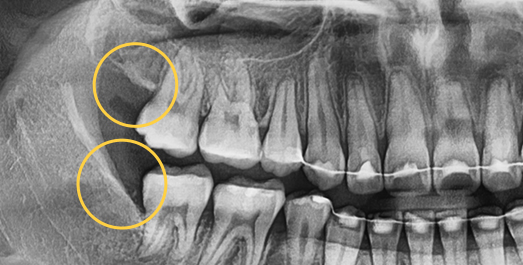

Even advanced cases

can be extracted.

With extensive experience in numerous advanced cases and a wide range of wisdom tooth extractions, you no longer need to go to a university hospital.